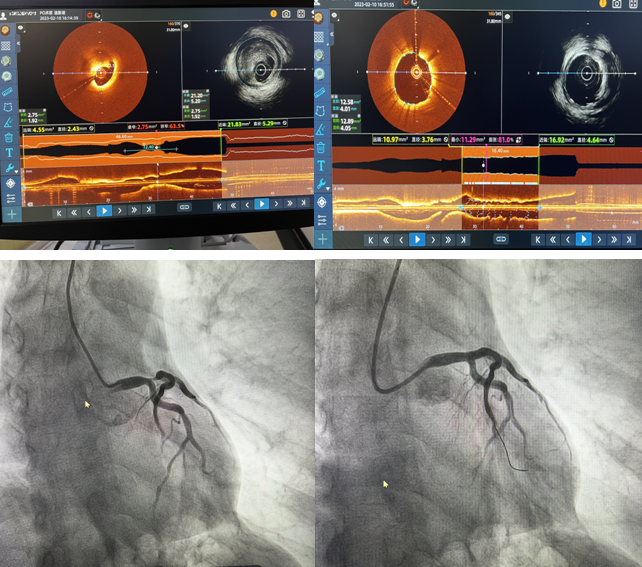

2月10日,我院心內二科主任郭明帶領的心臟介入團隊成功完成棗莊市首例IVUS-OCT雙模一體機全程指導PCI手術,標志著我院冠脈介入技術“精準化”又向前邁進了一大步。

患者,男,71歲,因“發作性胸痛5天”住院,肌鈣蛋白陽性,胸導聯T波倒置,臨床診斷為急性冠脈綜合征。冠脈造影檢查示:左前降支開口至左主干重度狹窄達90%,并累及對角支開口狹窄達80%。患者左主干及前降支開口同時存在嚴重狹窄,狹窄嚴重且存在不穩定斑塊,需更加精準支架定位與覆蓋病變,要保證支架的貼壁絕對良好,此處一旦形成亞急性血栓極有可能引起患者猝死,單純的冠脈影像并不能完全達到此種理想的指導作用。經過與患者家屬溝通,郭明主任和楊大成副主任組織團隊人員討論后,決定應用IVUS-OCT雙模一體機全程指導下實施病變血管介入手術。介入科李紅衛主任及盧慶林副主任進行圖像采集及分析解讀,確定冠脈內斑塊性質,精準判定血管直徑、病變長度和支架落腳點,指導選擇合適型號的支架,術后再次應用IVUS-OCT雙模一體機,觀察支架貼壁及膨脹良好,支架兩端無夾層,手術取得成功。

近年來如何進行優化的介入治療成為當前心血管領域的熱點。單純冠脈造影無論在定性診斷還是定量診斷上,都存在一定的局限性。IVUS具有更深的成像深度,但空間分辨率差;OCT具有更好的分辨率,能更好地對比斑塊成分,但其成像穿透深度有限。因此,單一的IVUS或OCT很難完全提供血管及斑塊內部完整的解剖學信息。IVUS-OCT一體機是集光學成像、聲學成像、硬件和軟件于一體的新型血管內成像技術,實現了利用一根導管、一次掃描成像就可以完成兩項血管內影像檢查,是精準PCI技術的進一步提升。